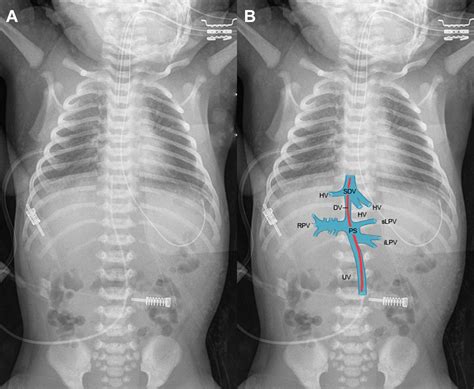

The Umbilical Venous Catheter is a thin, flexible tube that is inserted into the umbilical vein shortly after birth. This procedure is typically performed by a trained healthcare professional, such as a neonatologist or a neonatal nurse practitioner. The catheter is advanced until it reaches the inferior vena cava, providing a direct pathway to the heart and systemic circulation.

3. Insertion: The catheter is gently inserted into the umbilical vein, which is identified by its larger size and bluish color compared to the arteries. The catheter is advanced until it reaches the desired position, typically confirmed by ultrasound or X-ray.

5. Verification: The position of the catheter is verified using imaging techniques to ensure it is correctly placed in the inferior vena cava.